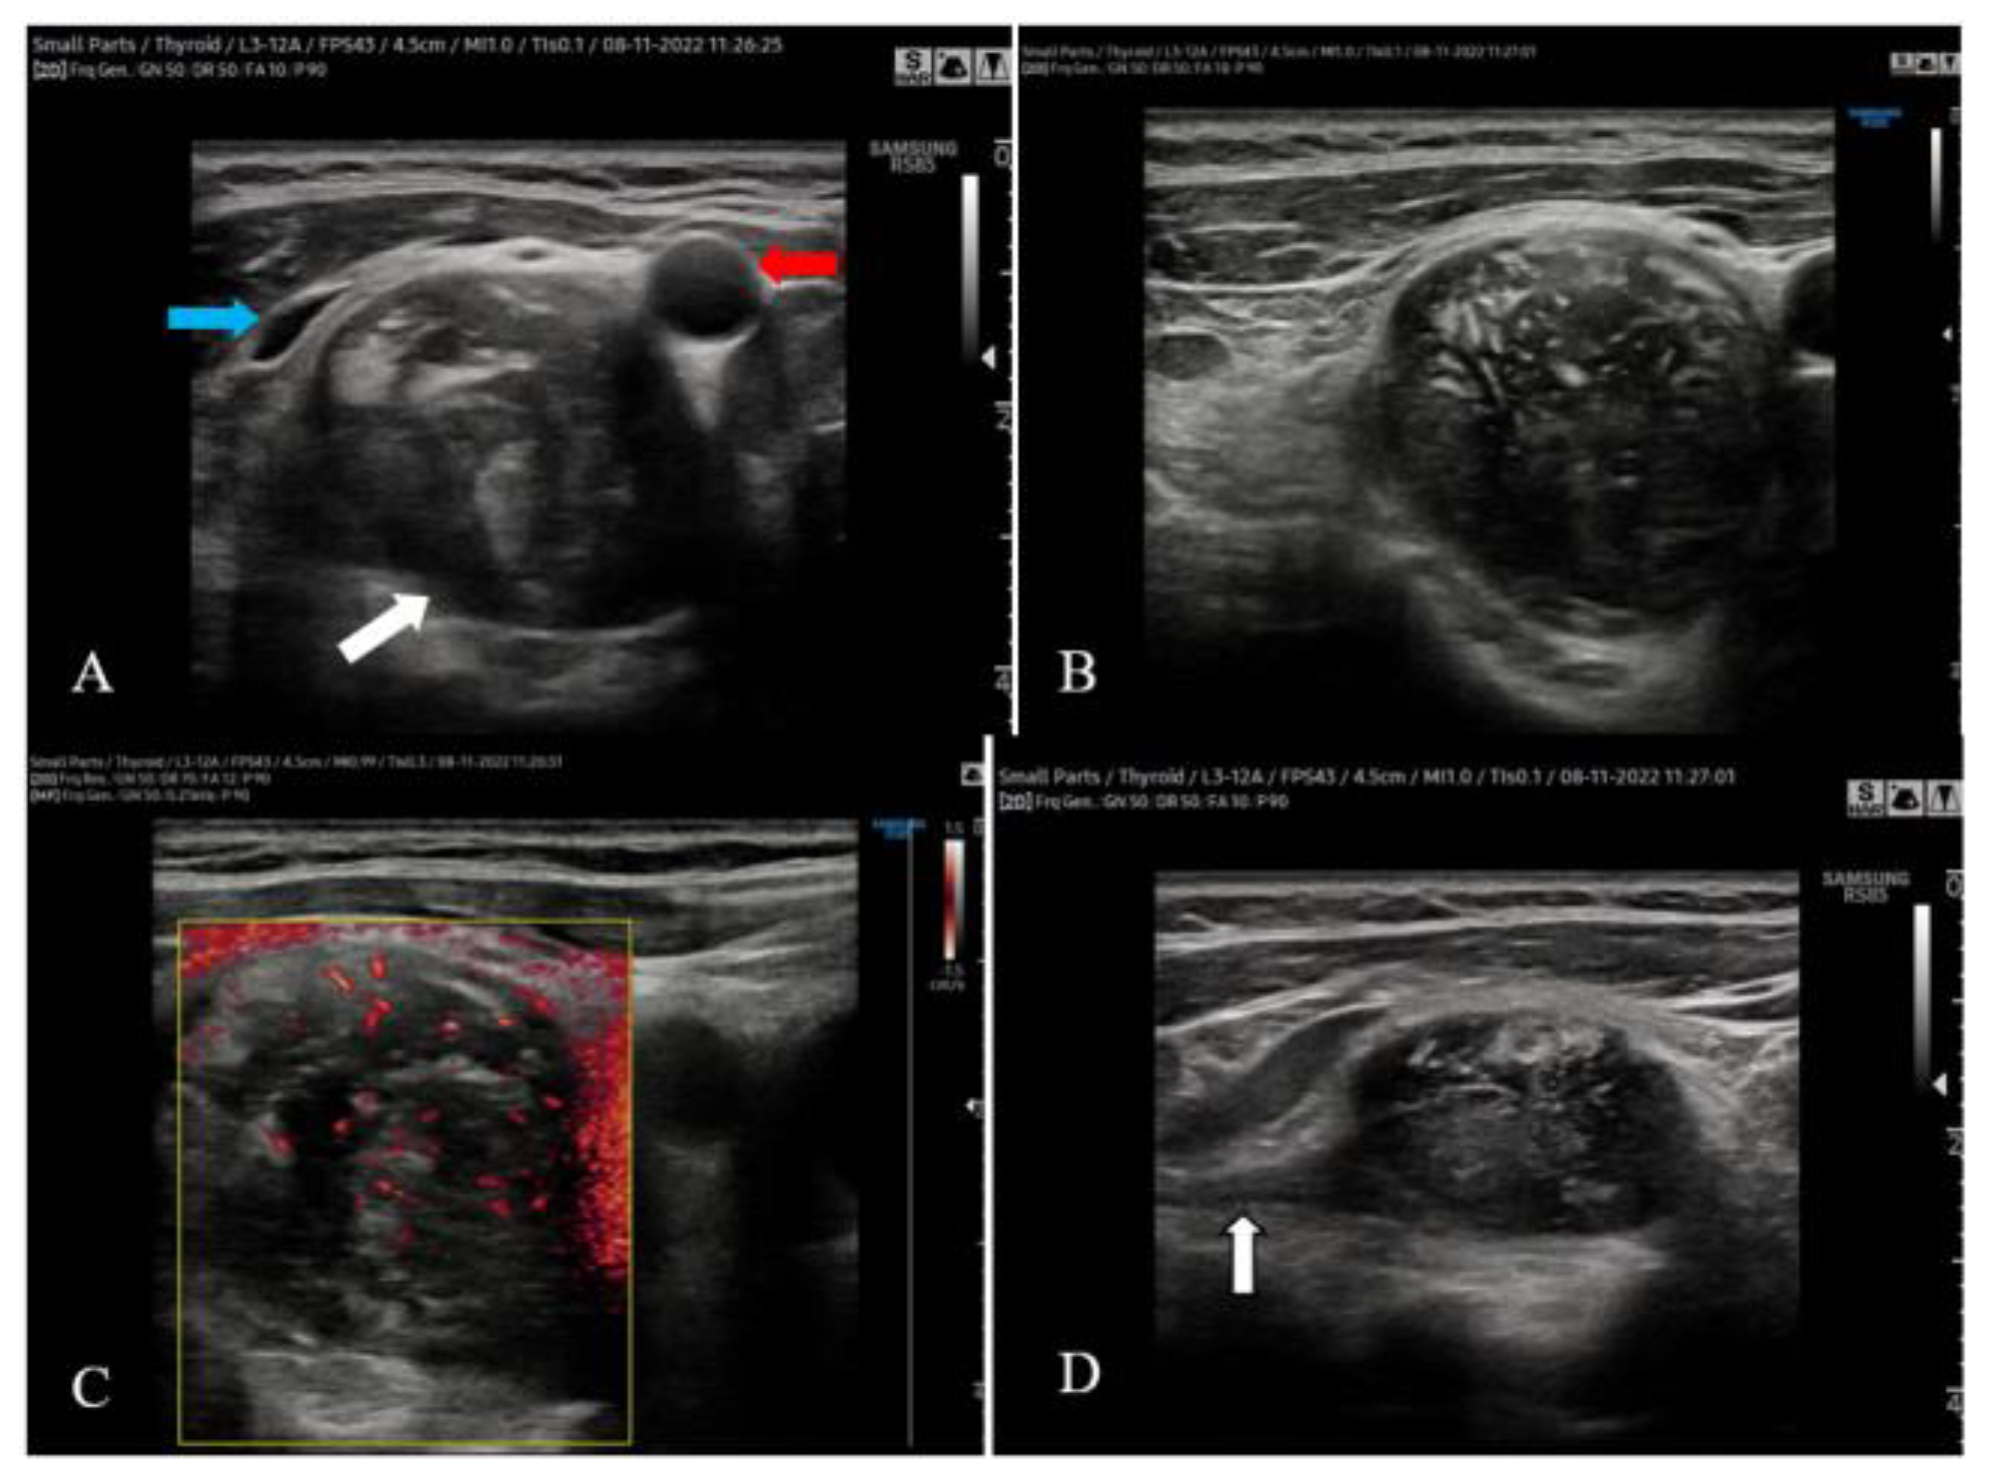

Having a preoperative diagnosis of nerve originating right cervical tumor, hypofunctional nodular goiter and primary hyperparathyroidism, the surgical procedure was performed under general anesthesia using a Kocher`s cervical incision. We confirmed the left lobe nodular goiter; we did not detect nodules in the isthmus or the right thyroid lobe. Behind the left thyroid lobe, we also identified an enlarged (10/5/5 mm) left inferior parathyroid gland. We explored the other parathyroid glands and these were normal. The right parapharyngeal mass was encapsulated, yellow-whitish and elastic. It was placed posteriorly and laterally to the right thyroid lobe and trachea. The tumor displaced forward and splayed the right CCA and IJV. The vagus nerve (also displaced laterally by the tumor) was dissected, being distinct of it (Figure 3).

Figure 3. Intraoperative photo – the right thyroid lobe (black arrow) was pulled medially by two Kocher forceps. A polyethylene drain was placed around the right IJV and a nylon thread was placed around the right vagus nerve. The right CCA (white arrow) and the right cervical tumor (dissected using an Overholt forceps) are also visible.